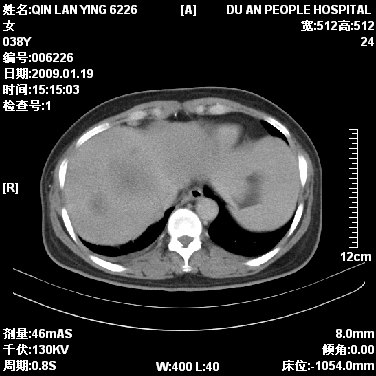

女,38岁,胸疼1个月。wbc:1万4

1)右肺中央型肺癌并右肺上叶阻塞性肺炎、节段性肺不张,纵隔淋巴结转移、右侧胸膜转移、肝脏转移。2)右侧胸腔少量积液。

1、右侧中央型肺癌并阻塞性肺不张,纵隔内、主动脉弓旁、右肺门淋巴结及肝脏转移可能性大,建议纤支镜进一步检查。

2、右侧胸腔积液。

本病例有几个容易诊断的地方:1、右肺上叶前段支气管闭塞,肺不张。2、淋巴结明显肿大。3、肝脏多个类圆形低密度影呈“牛眼征”改变,高度提示转移。

肺癌伴纵隔淋巴结转移、肝脏转移

从影像学角度分析      右肺上叶中央型肺癌,并阻塞性不张、肺炎,纵隔淋巴结、膈顶淋巴结转移。

肝内两个大小不等低密度结节,内可见更低密度影,首先考虑肝内转移瘤,但联想到患者wbc1万4,建议楼主还是做个增强比较明确,除外肝脓肿的可能。